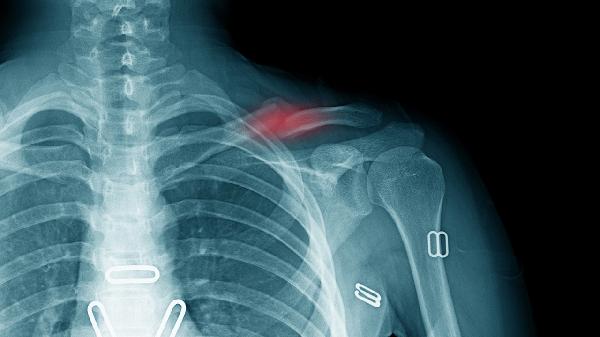

冠状动脉供血不足时可能出现压榨性胸痛,多由劳累诱发且休息后缓解。高危人群包括高血压、糖尿病患者,可能伴随冷汗和左肩放射痛。确诊需进行冠脉CTA检查,应急时可舌下含服硝酸甘油片。